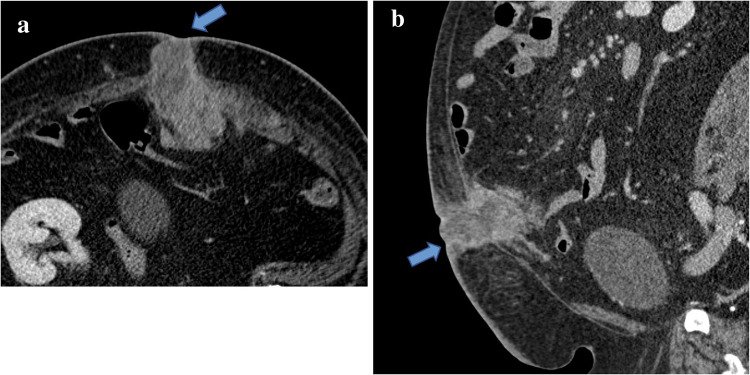

颗粒细胞瘤是一种罕见的源于雪旺细胞的软组织肿瘤。颗粒细胞瘤发生于前腹壁极为罕见,医学文献迄今仅报道了12例良性腹壁颗粒细胞瘤。我们报告一例上腹壁颗粒细胞瘤在最近产后35岁的妇女。根据患者的病史、近期产后表现和影像学表现,软组织肿瘤最初怀疑为硬纤维瘤。因此,在活检和切除后,良性颗粒细胞瘤的最终组织病理学诊断是非常罕见的。在此,我们讨论良性颗粒细胞瘤的独特表现及其诊断检查,包括影像学和组织病理学结果,以强调这种罕见实体在某些腹壁软组织肿块鉴别诊断中的可能性。

Granular cell tumors are uncommon soft tissue neoplasms derived from Schwann cells. It is extremely rare for granular cell tumors to be found in the anterior abdominal wall, with only 12 cases of benign abdominal wall granular cell tumors reported in the medical literature to date. We report a case of an upper abdominal wall granular cell tumor in a recently postpartum 35-year-old woman. Based on the patient's history, recent postpartum presentation, and imaging findings, the soft tissue tumor was initially suspected to be a desmoid tumor. Therefore, following biopsy and resection, the final histopathological diagnosis of benign granular cell tumor was quite unusual. Herein, we discuss a unique presentation of benign granular cell tumor and its diagnostic workup, including imaging and histopathologic findings, to highlight the possibility of this rare entity in the differential diagnosis of certain abdominal wall soft tissue masses.